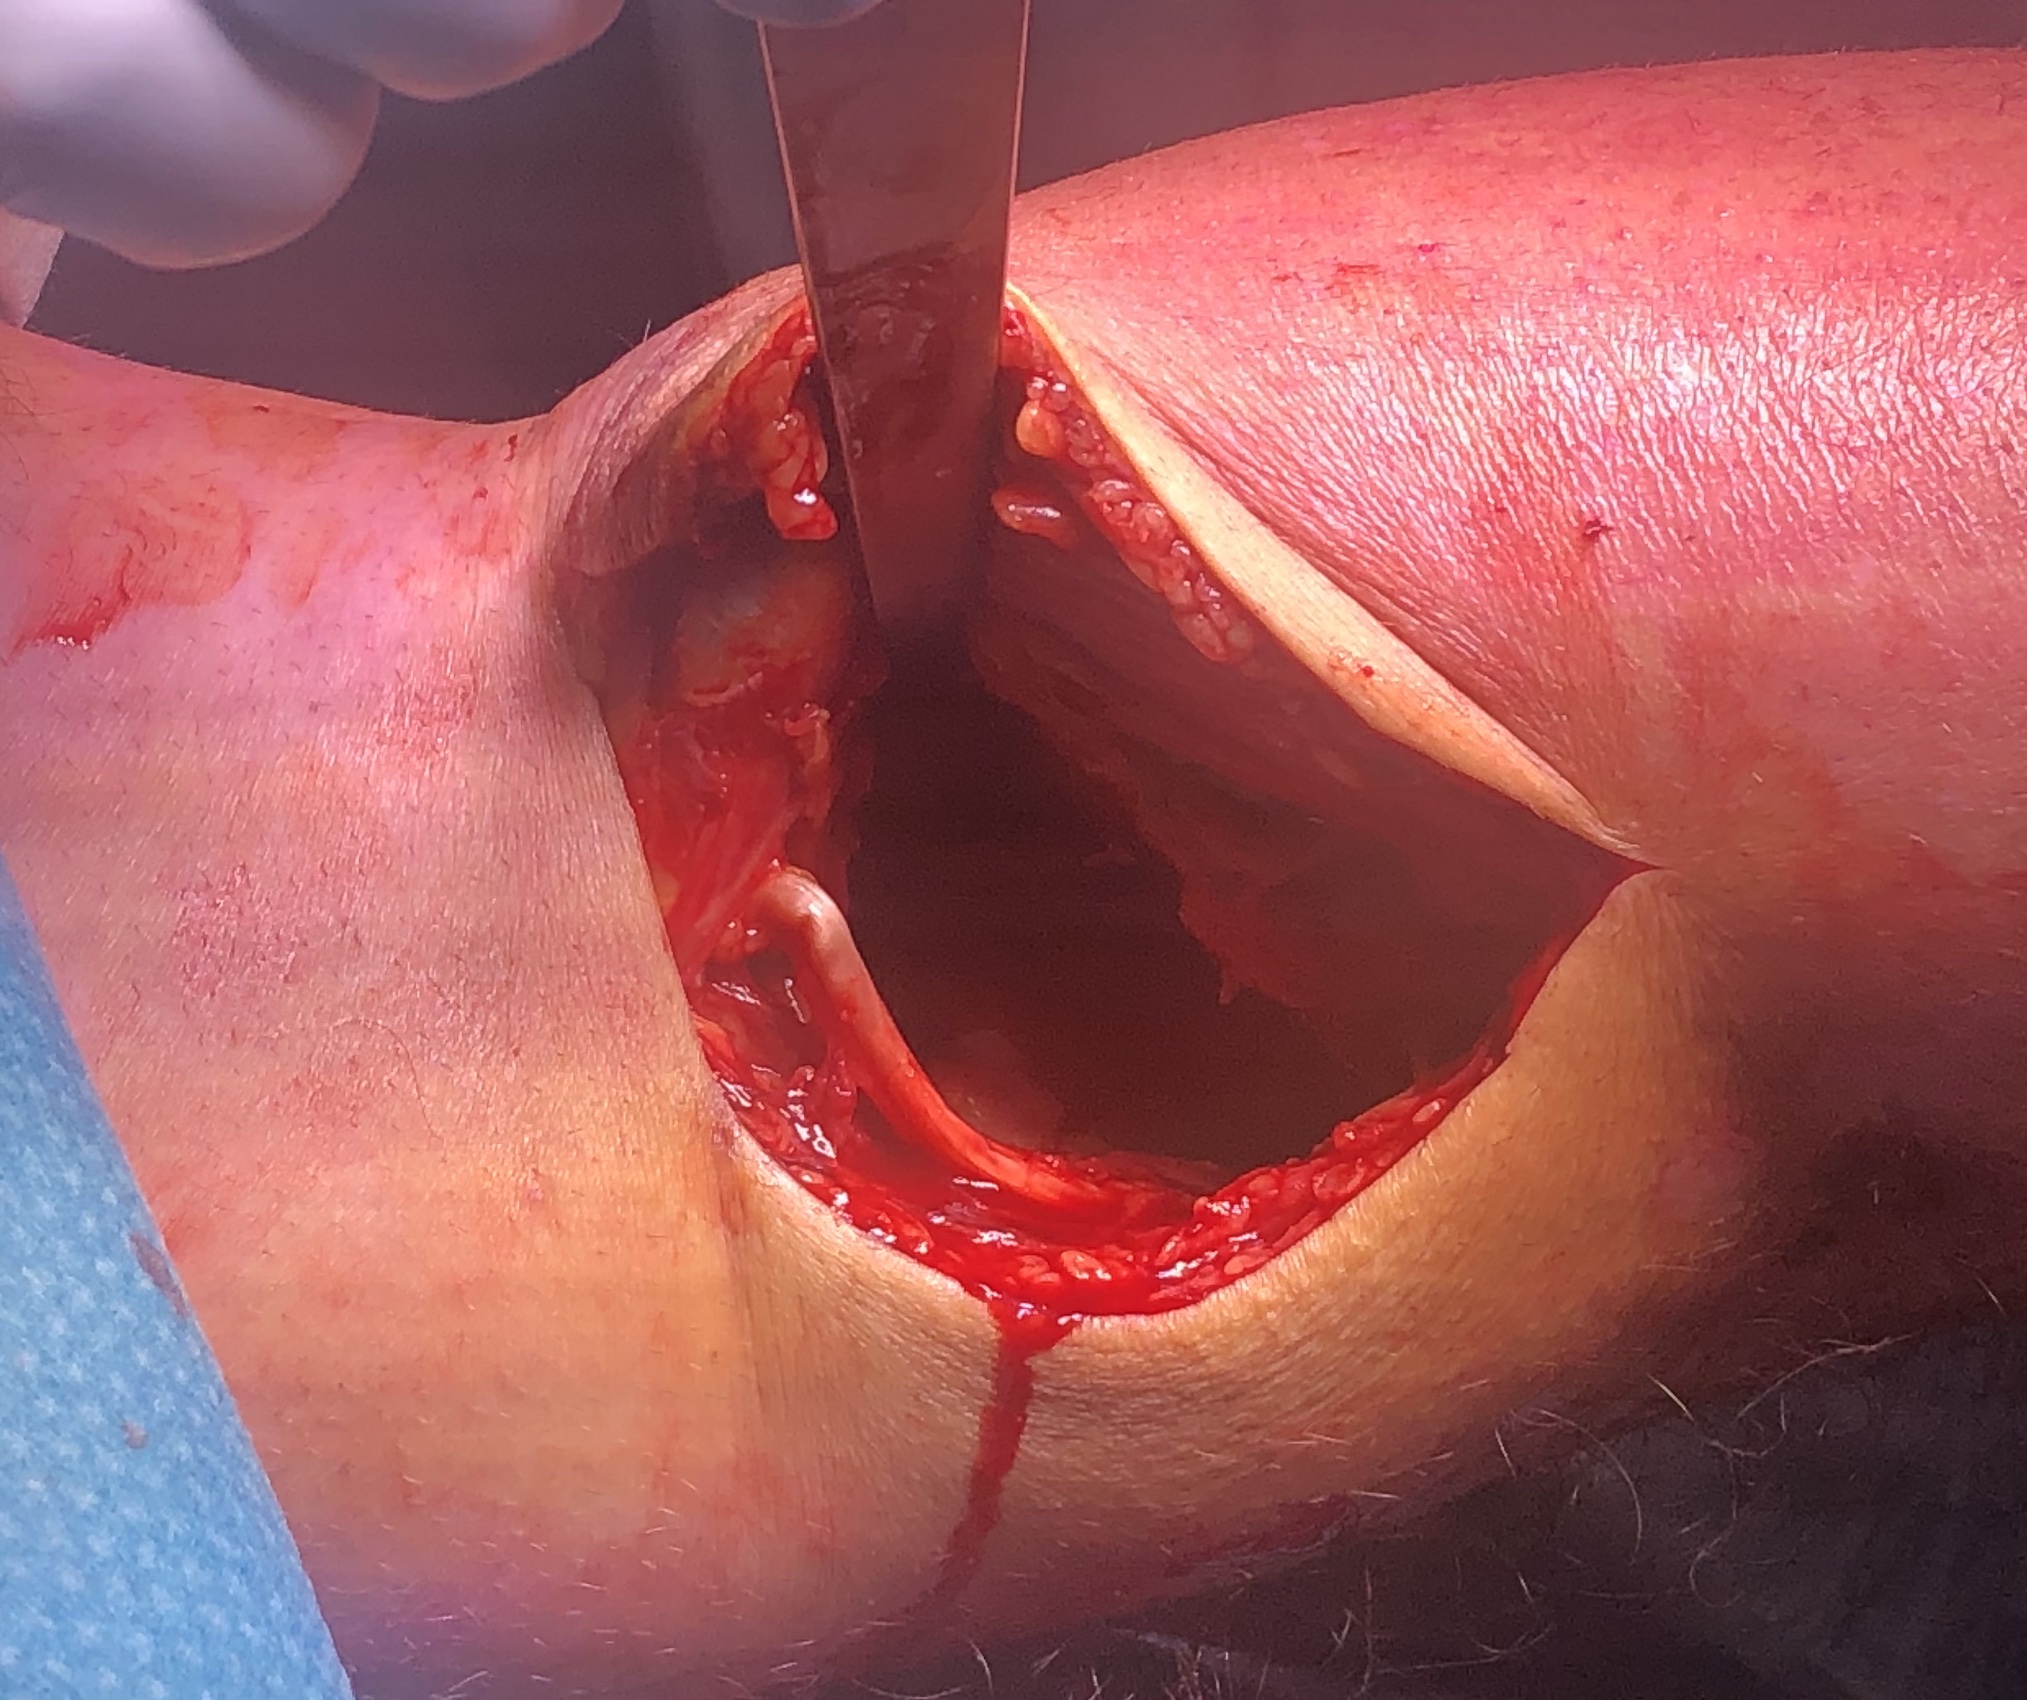

Approach

Anterolateral approach

- lateral longitudinal incision

- split ITB proximally

- open anterior fascia distally and elevate tibialis anterior from tibia

- perform submeniscal arthrotomy by incising capsule and coronary ligament from proximal tibia

- elevate capsule / ligament / and lateral meniscus via 1 vicryl stay sutures

- inspect joint and lateral meniscus via varus force

- can use femoral distractor

Technique

- elevate and restore joint line

- compress with bone reduction forcep

- stabilise joint line with 2 x 6.5 mm cannulated partially threaded screws

- check fluoroscopy

- restore alignment via application anatomically contoured 4.5 mm locking plate

- often use BG or substitutes under depression fractures laterally